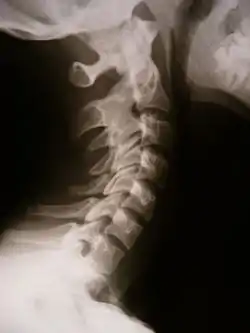

![]() X-ray showing synostosis in the cervical spine | |